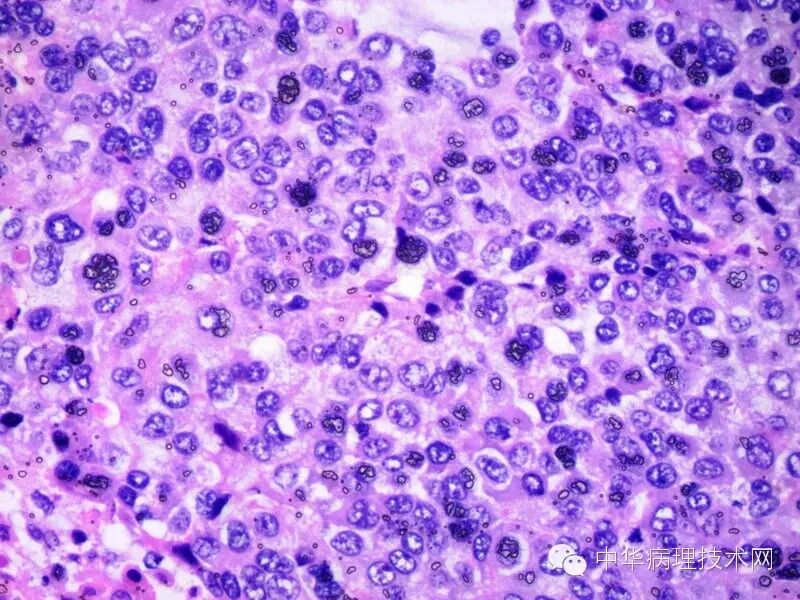

有些单位的切片中经常会看到这些黑色的颗粒,曾经有进修生告诉我:人体中所有的组织内都有黑色素,吓了我一身冷汗,问其原因,原来某大学医学院出的一本组胚图谱里每张照片都有这种黑色的颗粒。

其实就是切片经二甲苯透明后,在封片前切片干燥过了,树胶把空气封在切片上产生的不透明折光小泡,通常叫空气结晶。